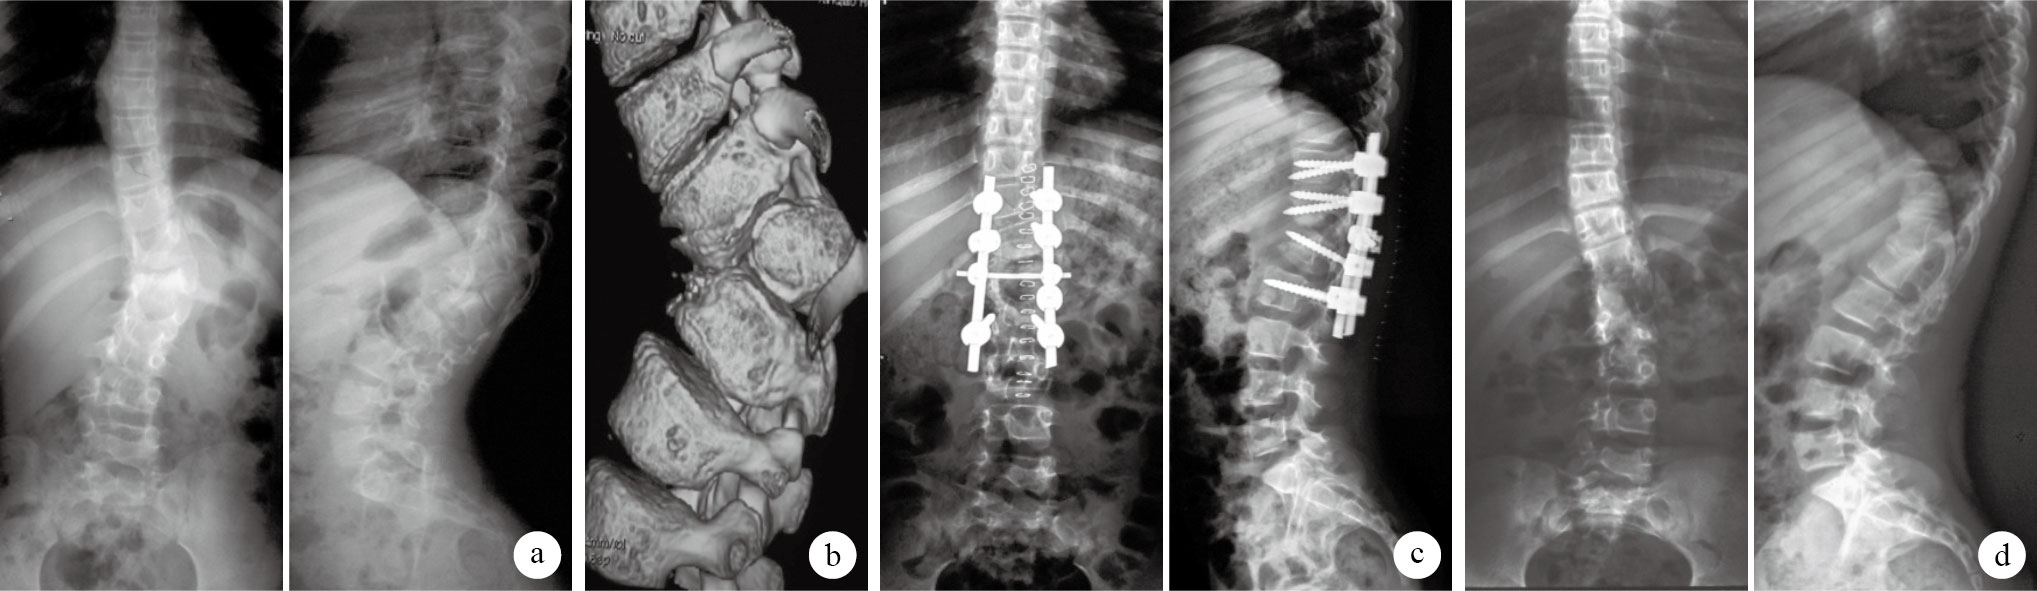

術后患者切口均Ⅰ期愈合。36例均獲隨訪,隨訪時間7~62個月,平均31.3個月。隨訪期間無椎弓根切割、釘棒斷裂、假關節形成等并發癥發生。末次隨訪時31例患者雙肩、雙髖達平衡狀態;B組3例患者雙肩稍傾斜,A、C組各1例患者雙髖未達平衡狀態。見圖 1。